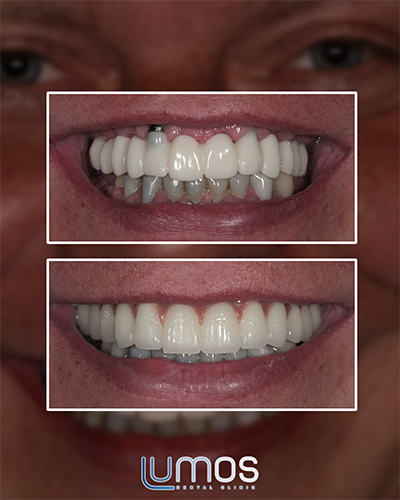

The “All-On-4 ™” dental implant treatment involves the fixing of acrylic veneers onto a prosthesis, which, in turn is attached to dental implants to ensure a perfect cosmetic result. The acrylic veneers used are extremely robust, and unlike a normal prosthesis, will blend the gingival colour seamlessly with the patient’s own palate, providing a flawless and comfortable fit. After the two-day treatment has been completed the patient will be able to return to their usual social life bearing a wonderfully perfect smile.

- The final result will offer comfort, and the aesthetically designed result will increase the patient’s quality of life.